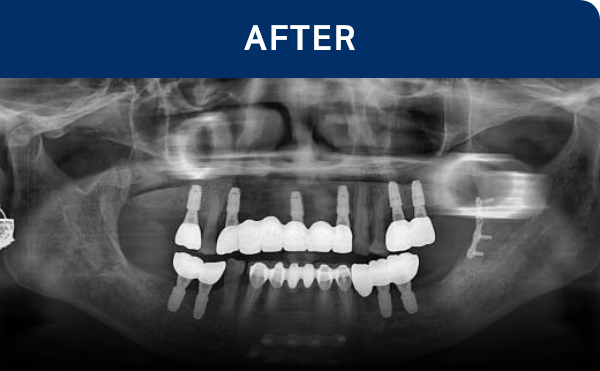

清晰可见的成果,

就是新吉种植牙

科值得信赖的证明.